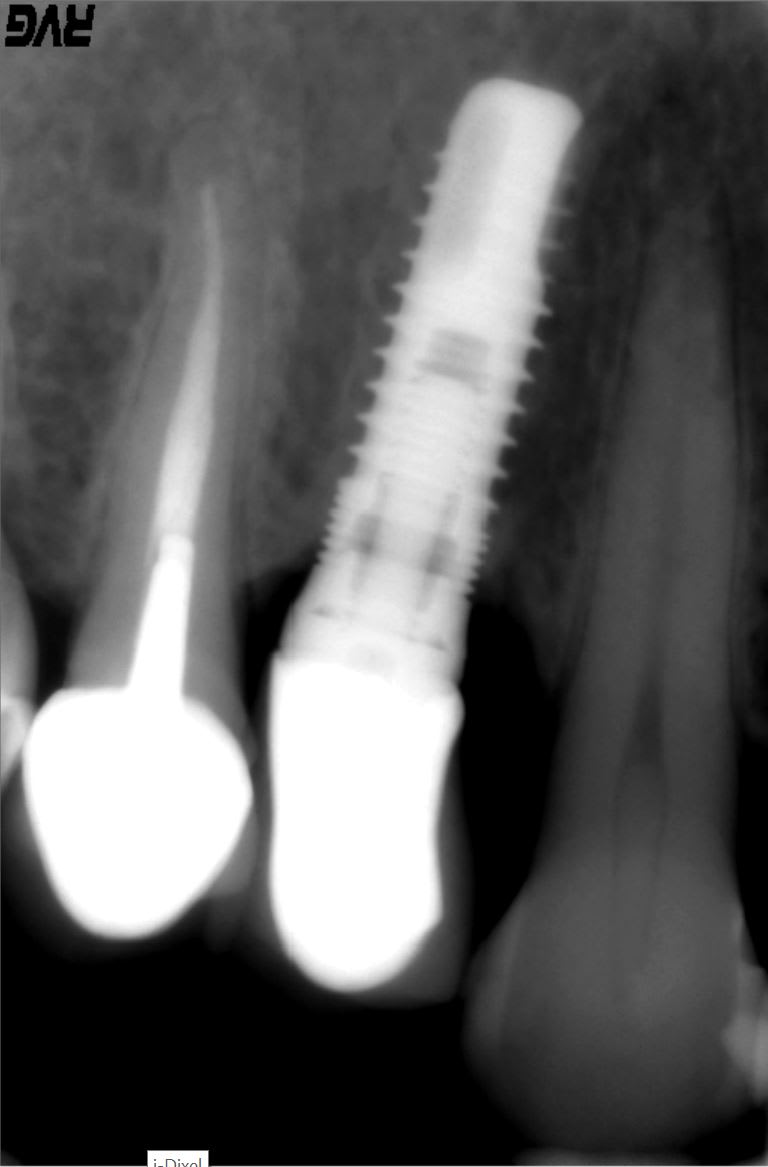

Quel est cet implant ?

Serf EVL N

Maintenant Global D